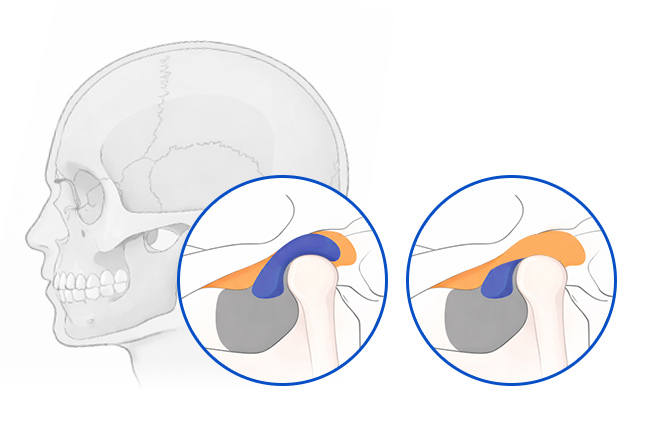

턱관절이 손상되면?

관절원판(두 뼈 사이에 위치한 탄력 있는 디스크, 관절의 충격을 완화하고

부드러운 움직임을 돕는 역할) 이 앞으로 밀리거나 찢어질 수 있고,

관절낭 및 인대에 염증이 생기거나, 근육 불균형으로 인해 턱 움직임 자체가 왜곡되기도 합니다.

이런 변화는 턱 소리, 통증, 개구 장애, 두통, 안면통증 등으로 이어집니다.